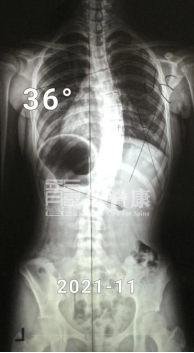

在2021年的春天,13岁的小墨同学和她的父母来到了门诊诊查,原因是2019年的10月份,她在当地医院检查确诊为脊柱侧弯,当时做了一段时间的推拿按摩,但体态问题依然没有改善。

因脊柱不同节段骨骼结构的特殊性,胸弯比腰弯难矫正多了。但值得庆幸的是,小墨当时月经来潮刚满半年,身体还处于生长发育高峰期,还有一定的矫正空间。从那时开始,小墨便开始每天穿戴GBW支具22小时,配合施罗斯训练1小时以上的长期治疗。

在最初的一年里,小墨坚持每3个月回来复查体态以及调整支具。3个月复查时,脱支具4小时后的X光片显示,她的胸弯度数已经从50°减至39°,且剃刀背都有明显改善,右背部剃刀背由14°减至7°,左腰部剃刀背由12°减至8°。